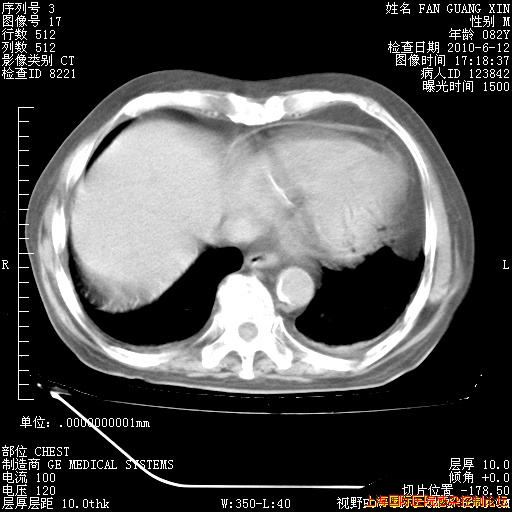

6月12日纵膈窗